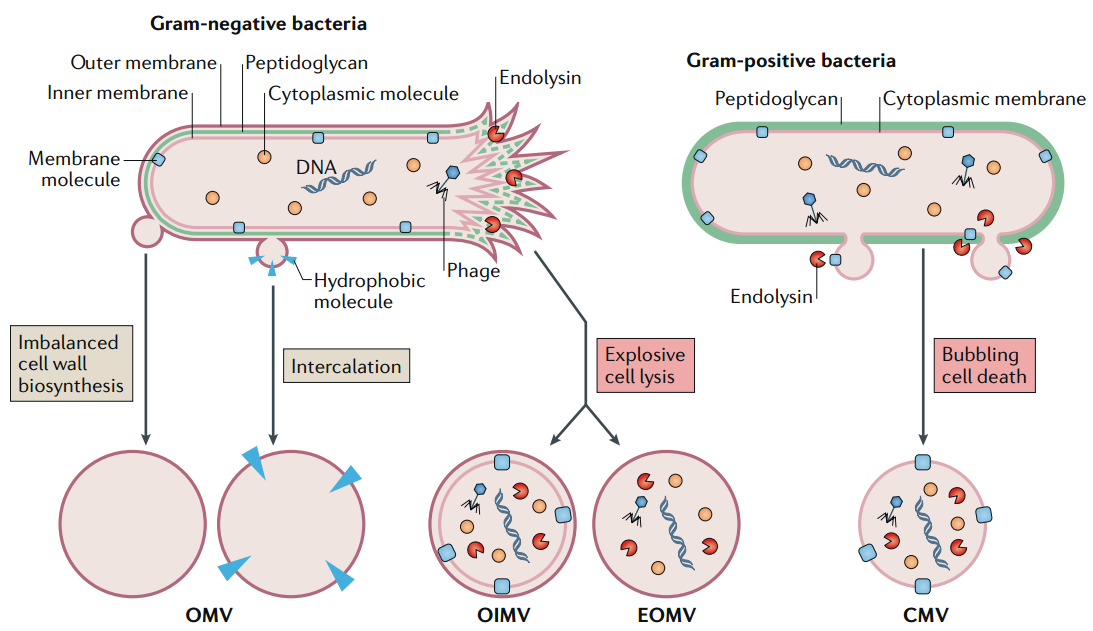

查看详情 细菌生物膜破坏抗体快速用于治疗囊性纤维化患

细菌生物膜破坏抗体快速用于治疗囊性纤维化患

美国食品药品监督管理局 (FDA) 已授予 CMTX-101 快速通道和合格传染病产品 (QIDP) 称号,用于治疗囊性纤维化患者的慢性...